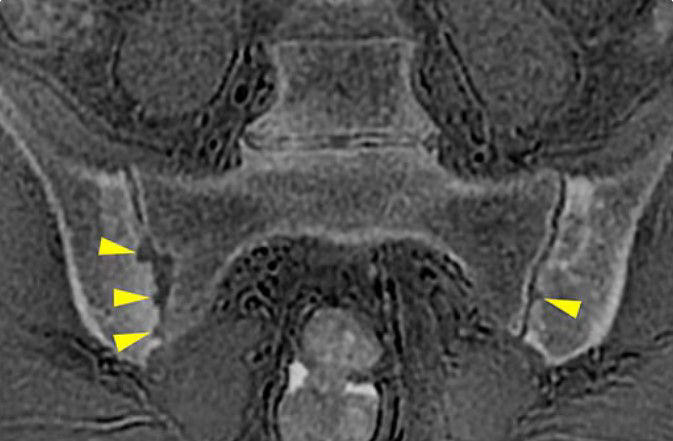

CT-like image contrast without ionizing radiation

MR bone imaging provides a CT-like image contrast without ionizing radiation, making it an attractive alternative for pediatric and pregnant patients where ionizing radiation is a concern. In addition, it provides a welcome alternative when longitudinal CTs are required, particularly when low-dose CT systems are unavailable.

oZTEo images can be used for geometric and morphologic measurements, such as in routine FAI in the hip.  These results have been published in The American Journal of Sports Medicine, 2019: 47(14):  3460-3468.